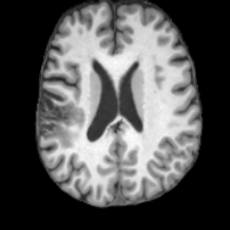

(a)PathologicalInput ImageSynthSR [18]Brain-ID [28]UNA [30]USBHealthyGround TruthRefer to captionRefer to captionRefer to captionRefer to captionRefer to captionRefer to captionRefer to captionRefer to captionRefer to captionRefer to captionRefer to captionRefer to captionRefer to captionRefer to captionRefer to captionRefer to captionRefer to captionRefer to captionRefer to captionRefer to captionRefer to captionRefer to captionRefer to captionRefer to caption(b)HealthyInput ImageConditionalLesion MaskUNA [30]USBRefer to captionRefer to captionRefer to captionRefer to captionRefer to captionRefer to captionRefer to captionRefer to captionRefer to captionRefer to captionRefer to captionRefer to captionRefer to captionRefer to captionRefer to captionRefer to caption

Figure 5: Comparison of bidirectional brain editing. (a) pathology-to-healthy, the circles and arrows highlight lesion regions and unsuccessful reconstructions; (b) healthy-to-pathology. Note that SynthSR and Brain-ID cannot perform healthy-to-pathology editing.

Pathology-to-Healthy Editing. Fig. 5 (a) presents comparison results on four input brain images with lesions of varying sizes, shapes, and densities. All competing models, although specialized for healthy brain image synthesis, struggle to reconstruct pathological regions, especially near lesion boundaries. In contrast, USB accurately reconstructs the corresponding healthy brain, even in challenging cases with large, high-density lesions where normal brain structures are almost completely obscured (last row). Tab. 2 provides a quantitative comparison for pathology-to-healthy editing, where USB achieves the best performance across all three datasets, demonstrating the effectiveness of its unified framework in reconstructing healthy brains from pathological inputs. Additional results are in Suppl. B.